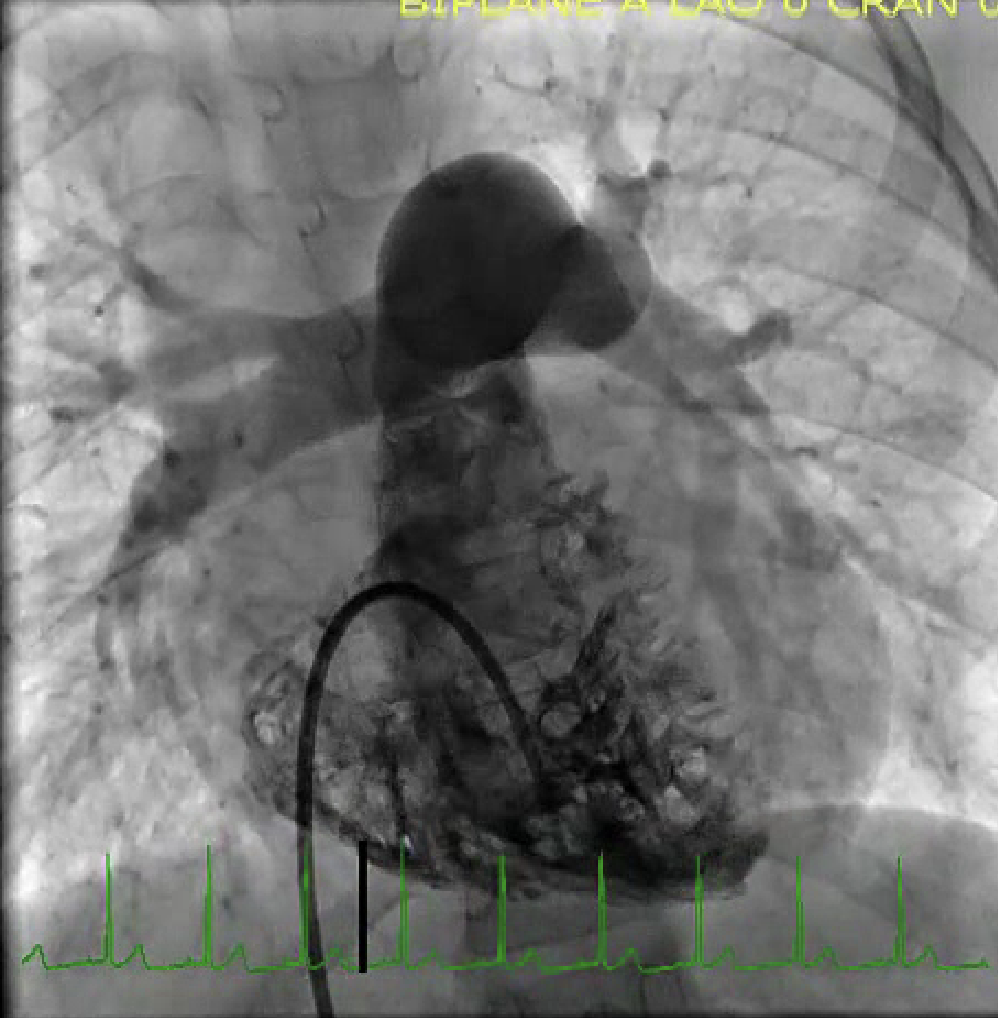

Describe the findings:

*****Dx: HCM with prior apical MI –> LV apical aneurysm

******mid-cavity obliteration during systole –> LVOTO

*******mechanism of MR in this setting –> systolic anterior motion of anterior MV